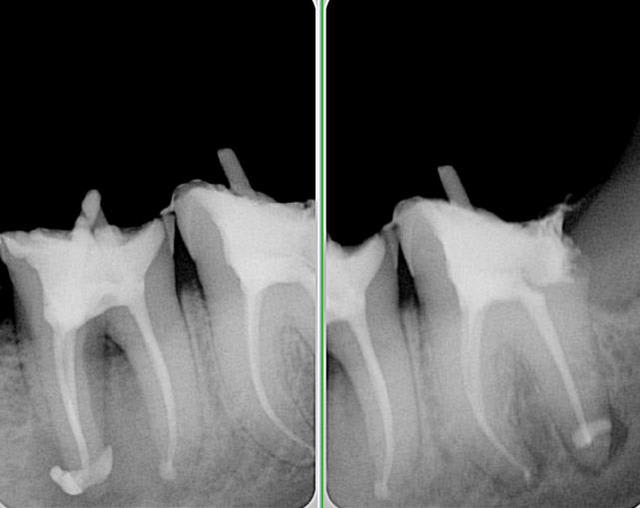

plus d'une heure pour essayer de sauver ces 37 et 38...

mais etait ce vraiment suffisant? cicatrisation possible?

60 mn environ pour ces 2 là, le canal mv2 augmente le temps d'exéctution de 15 à 30 mn surtout si l'entrée est proche du mv1. Il n'y a pas photo entre la préparation canalaire du r25 VS f2 protaper.